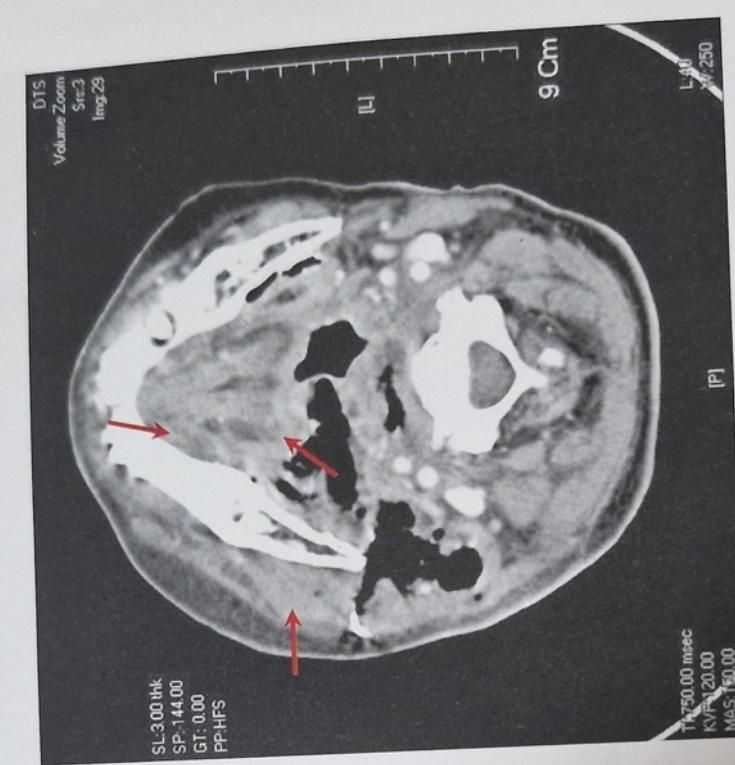

하악골의 수평평면으로 본 컴퓨터단층촬영사진으로 후인두간극과 척추전간극에 농양이 퍼져있는 양상으로 기도가 꺾여있는 모습을 관찰할수있다고 나와있는데 무슨 소리인지 모르겠습니다ㅜㅜ 쉽게 설명해주실분 구합니다ㅜㅜㅜㅜ

말그대로 염증이 목쪽까지 퍼져서 기도를 누르고 잇다는 말입니다. 염증이 기도를 누르니 기도가 꺽여 잇는것처럼 보이는겁니다.

염증으로 인해서 고름이 두경부의 근육사이의막에 퍼졌다는 의미 입니다 이 고름으로 인해서 숨을 쉬는 기도 부위가 눌리고 있다는 의미 입니다.